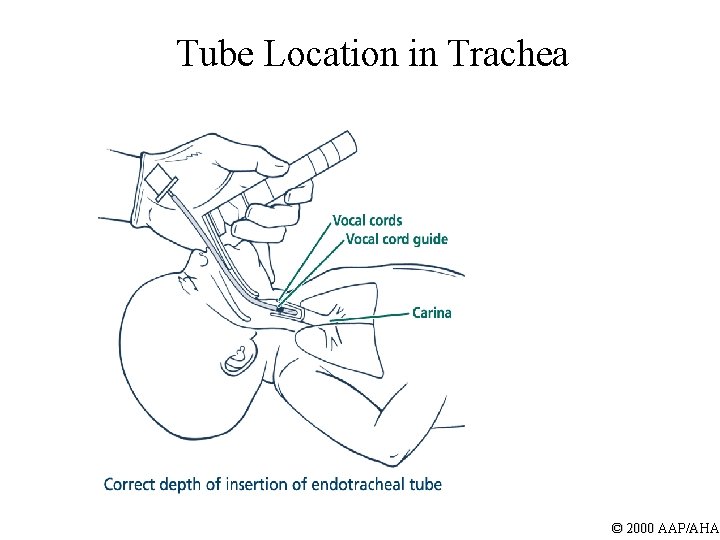

Tube Location in Trachea © 2000 AAP/AHA